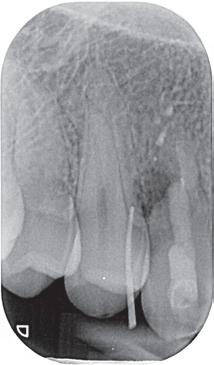

We zijn begonnen met de 13 en hebben een week later de 12 en de 11 behandeld. Bij de 13 kon een volledig necrotische pulpa worden geëxtirpeerd (afbeelding 7). Aangezien we aan de vitaliteit van de 12 en 11 twijfelden, hebben we eerst een proefboring uitgevoerd en beide elementen bleken volledig necrotisch.

De kanalen zijn ultrasoon gespoeld met 2% NaOCl en EDTA onder isolatie van rubberdam. Het kanaal van de 13 is gevuld met MTA (afbeelding 8), omdat er sprake was van een niet-afgevormde radix. Dit is afgedekt met een laagje Vitrebond. In de 12 en 11 hebben we guttapercha en AH26 aangebracht via een hybride vultechniek (afbeelding 9).